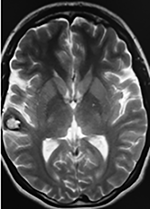

Paciente femenino de 29 años de edad con historial de cefalea crónica que presenta súbitamente disdiadococinesia y dismetría izquierda.

El estudio de RMN presenta una lesión bien circunscrita en hemisferio cerebeloso izquierdo con periferia de predominio hiperintenso en T1 y T2, y centro hipointenso, edema perilesional mínimo, así como una imagen de un vaso venoso alimentador que recorre hacia el ángulo pontocerebeloso izquierdo.

El estudio de control de RMN se observa la brecha quirúrgica y ausencia de lesión (figs. 1, 2 y 3).

Figura 2:

Cortes axiales en ponderación T1, cambios postquirúrgicos.